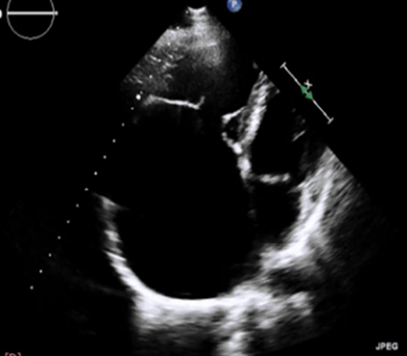

Exámenes complementarios: Electrocardiograma, evidencia fibrilación auricular, bloqueo completo de rama derecha, trastorno de la repolarización ventricular, Figura 1. Ecocardiograma reporta FEVI: 39%, rectificación del septo interventricular por sobrecarga de cámaras derechas, aumento del volumen atrial derecho, discreta estenosis mitral, válvula tricúspide de implantación baja, anomalía de Ebstein, reflujo tricúspide importante, hipertensión pulmonar moderada, formen oval patente, Figura 2. Radiografía con proyección posteroanterior de tórax reveló cardiomegalia grado IV, Figura 3. Ecografía de Abdomen, concluye dilatación de las venas hepáticas secundario a falla cardíaca congestiva, asociado a leves cambios en la eco textura del parénquima hepático por lo que se debería considerar hepatopatía congestiva, además de colelitiasis, Figura 4.

Figura 2 Ecocardiograma, archivo de la paciente. Se observa válvula tricúspide de implantación baja en el ventrículo derecho, lo cual produce aumento del diámetro de la aurícula derecha a expensas del ventrículo derecho (atrialización ventricular derecha).

La fisiopatología de esta anomalía está dada por la disfunción de la válvula tricúspide lo cual desencadena una falla ventricular derecha con signos de sobrecarga de presión o volumen en presencia de valvas estructuralmente anormales (9), en nuestro caso se aprecia sobrecarga de cámaras derechas, aumento del volumen atrial derecho, tricúspide de implantación baja, y el importante reflujo tricúspide lo cual se ajusta a las características típicas de la anomalía y los eventos fisiopatológicos que reporta la literatura.

Los criterios ecocardiográficos utilizados para identificar una anomalía de Ebstein abarcan el desplazamiento apical observado en las inserciones valvulares septal y posterior de la válvula tricúspide, junto con el desplazamiento del anillo tricúspide funcional en dirección anterior y descendente, lo que lleva a la atrialización del ventrículo derecho. Además, cabe destacar que la anomalía cardíaca predominante relacionada con esta afección en los pacientes recién nacidos es la comunicación interauricular (16). En nuestro caso, desde la perspectiva ecocardiográfica la paciente presentó sobrecarga de cámaras derechas, aumento del volumen atrial derecho, discreta estenosis mitral, válvula tricúspide de implantación baja e importante reflujo tricuspídeo lo que a su vez generó una hipertensión pulmonar moderada, no obstante, en la paciente también se practicó un eco de abdomen en el cual se reportó hepatopatía congestiva secundaria a una falla cardíaca intrínseca atribuida a la anomalía de Ebstein.